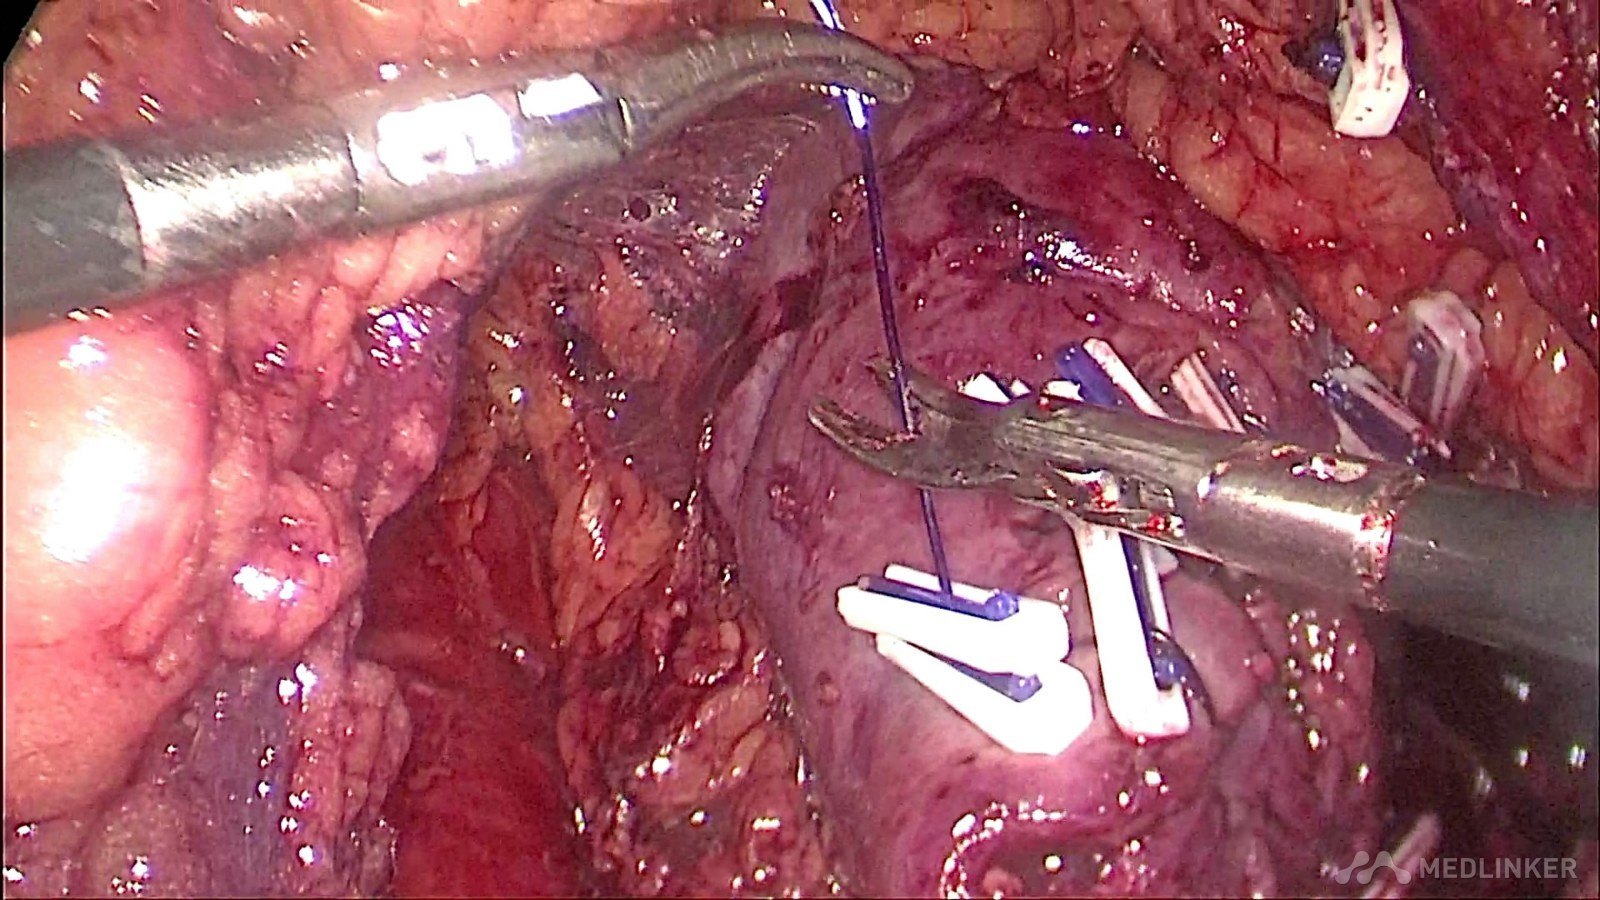

夹闭肾段动脉,防止出血,并电凝肿瘤切面减少切缘阳性率的发生

可吸收线连续缝合残留肾脏创面,减少出血,促进肾功能的保护

缝合完毕后,开放右肾动脉,仔细检查创面渗血情况和缝合张力,必要时可加针缝合减少渗血